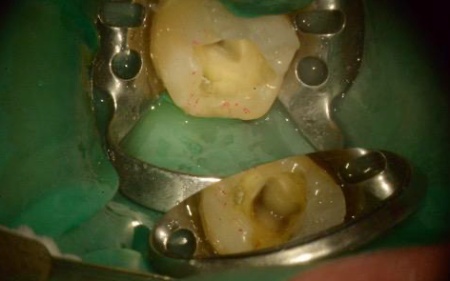

まず、既存の詰め物を除去したうえでラバーダムを装着し、治療する歯のみを隔離して清潔を保ちながら処置できる状態を整えます。

マイクロスコープを用いて根管の内部を確認したところ、この歯には4本の根管がありました。

それぞれの根管内の感染組織や汚れを専用器具で丁寧に除去し、薬液による洗浄と消毒を繰り返し行っています。